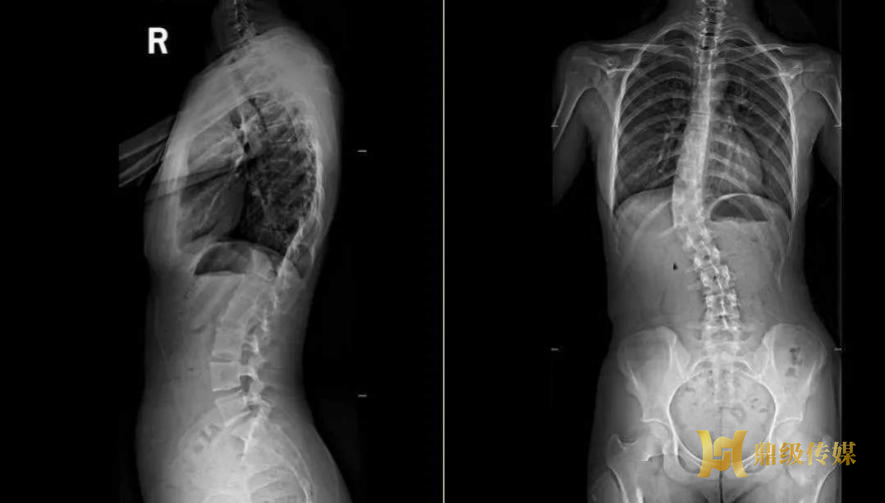

10岁的小雨(化名)刚上四年级,9岁时学校体检已查出轻度特发性脊柱侧弯,Cobb角18°,医生建议定期复查、姿势矫正与康复训练,必要时佩戴支具。父母觉得“只是坐姿不好、不痛不痒”,认为孩子长大自然会好,既没复查也没干预。进入10岁生长高峰期,小雨脊柱快速进展:双肩明显不等高、右侧肩胛骨凸起、弯腰时出现剃刀背,走路易累、跑步气喘,夏天不敢穿贴身衣服,性格变得自卑内向。女性脊柱侧弯是一种悄悄进展的脊柱畸形,在女性身上尤为高发。很多人以为,脊柱侧弯只是青少年的“体态问题”,成年后就会稳定不变。事实恰恰相反:女性脊柱侧弯,是贯穿一生的健康隐患。从青春期到怀孕生子,再到更年期,有三个阶段侧弯极易快速加重,轻则腰背痛、体态歪斜;重则神经压迫、影响心肺功能,甚至不得不接受手术。今天,将所有女性同胞们科普:一生要警惕的三个脊柱侧弯加重期,早知道、早干预,守护脊柱健康!

重点人群:10~14岁女孩,月经初潮前后1~2年。青春期是脊柱侧弯进展最快、最危险的阶段,女孩发病率远高于男孩。这个时期身高突增,脊柱生长速度远超肌肉平衡能力,侧弯角度会随骨骼发育一路飙升。尤其月经初潮前后,是监测黄金窗口:初潮前脊柱快速生长,侧弯进展迅猛;初潮后若未及时干预,短短数月角度就可能大幅增加。

临床中不乏这样的案例:初潮前侧弯仅20°,5个月内迅速增至45°,一年后逼近50°,直接面临手术风险。很多家长一句“长大就好了”,恰恰错过了最佳矫正时机。